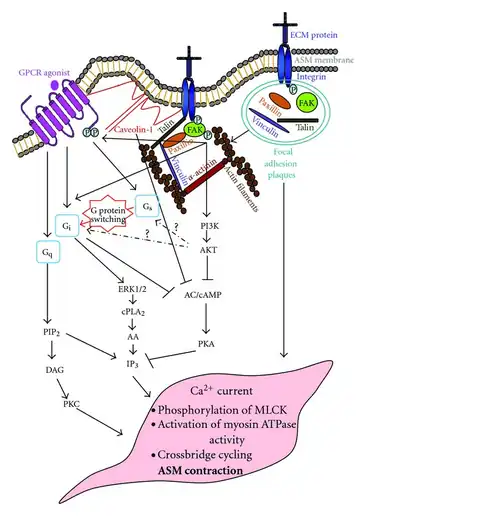

The structure of α receptors is a classic G protein–coupled receptors (GPCRs) consisting of 7 transmembrane domains, which form three intracellular loops and three extracellular loops.[2] These receptors couple to heterotrimeric G proteins composed of α, β, and γ subunits.[2] Although both of the α receptors are GPCRs, there are large differences in their mechanism of action. Specifically, α1 receptors are characterized as Gq GPCRs, signaling through Phospholipase C to increase IP3 and DAG, thus increasing the release of calcium. Meanwhile, α2 receptors are labeled as Gi GPCRs, which signal through adenylyl cyclase to decrease cAMP.[38]

Because the α1 and α2 receptors have different mechanisms of action, their antagonists also have different effects.[39] α1 blockers can inhibit the release of IP3 and DAG to decrease calcium release, thus, decreasing overall signaling. On the other hand, α2 blockers prevent the reduction of cAMP, thus leading to an increase in overall signaling.